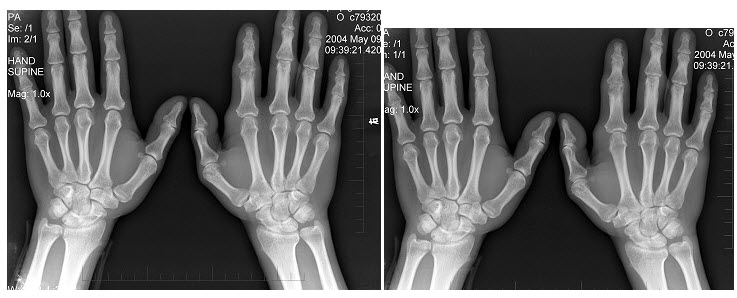

59、单项选择题

男,19岁,双手肿痛2年,晨僵,结合图像,最可能诊断是()

A.痛风

B.强直性脊柱炎

C.类风湿关节炎

D.退行性关节炎

E.未见异常